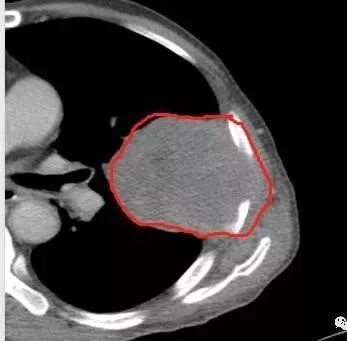

鳞癌因为侵袭性力较强,容易直接侵犯胸膜、胸壁,而周围型肺癌侵犯胸壁的90%癌肿是鳞癌,这也是鳞癌的一个特征性表现。邻近胸壁的脂肪层消失,胸壁肿块形成或有肋骨皮髓质边界不清的侵蚀破坏(而非边缘硬化或崩解)是瘤体向周围直接侵犯的可靠征象。

鳞癌因为破坏力强,其内可见灶样坏死区,坏死边界不清,其内血管破坏彻底。

肉瘤样癌也好发于中老年人,与吸烟关系密切。肿块体积往往较大,也是好发于胸膜下伴胸壁侵犯,也容易发生坏死,与周围型鳞癌的主要鉴别点在于支气管的关系和病灶内强化的情况。肉瘤样癌以环状强化为主,病灶周边多以癌组织为主,血供丰富,病灶中心区则以肉瘤成分为主,血供较差,易出现粘液样变性、坏死、出血,坏死边界清楚。

肺肉瘤是少见的来源于间叶组织来源的肿瘤,起源于肺间质、支气管壁、支气管软骨等间叶组织,往往体积较大,边缘光整,无明显分叶、毛刺,也会大片坏死,也会有胸壁的侵犯,有时与肺癌、肉瘤样癌很难鉴别。